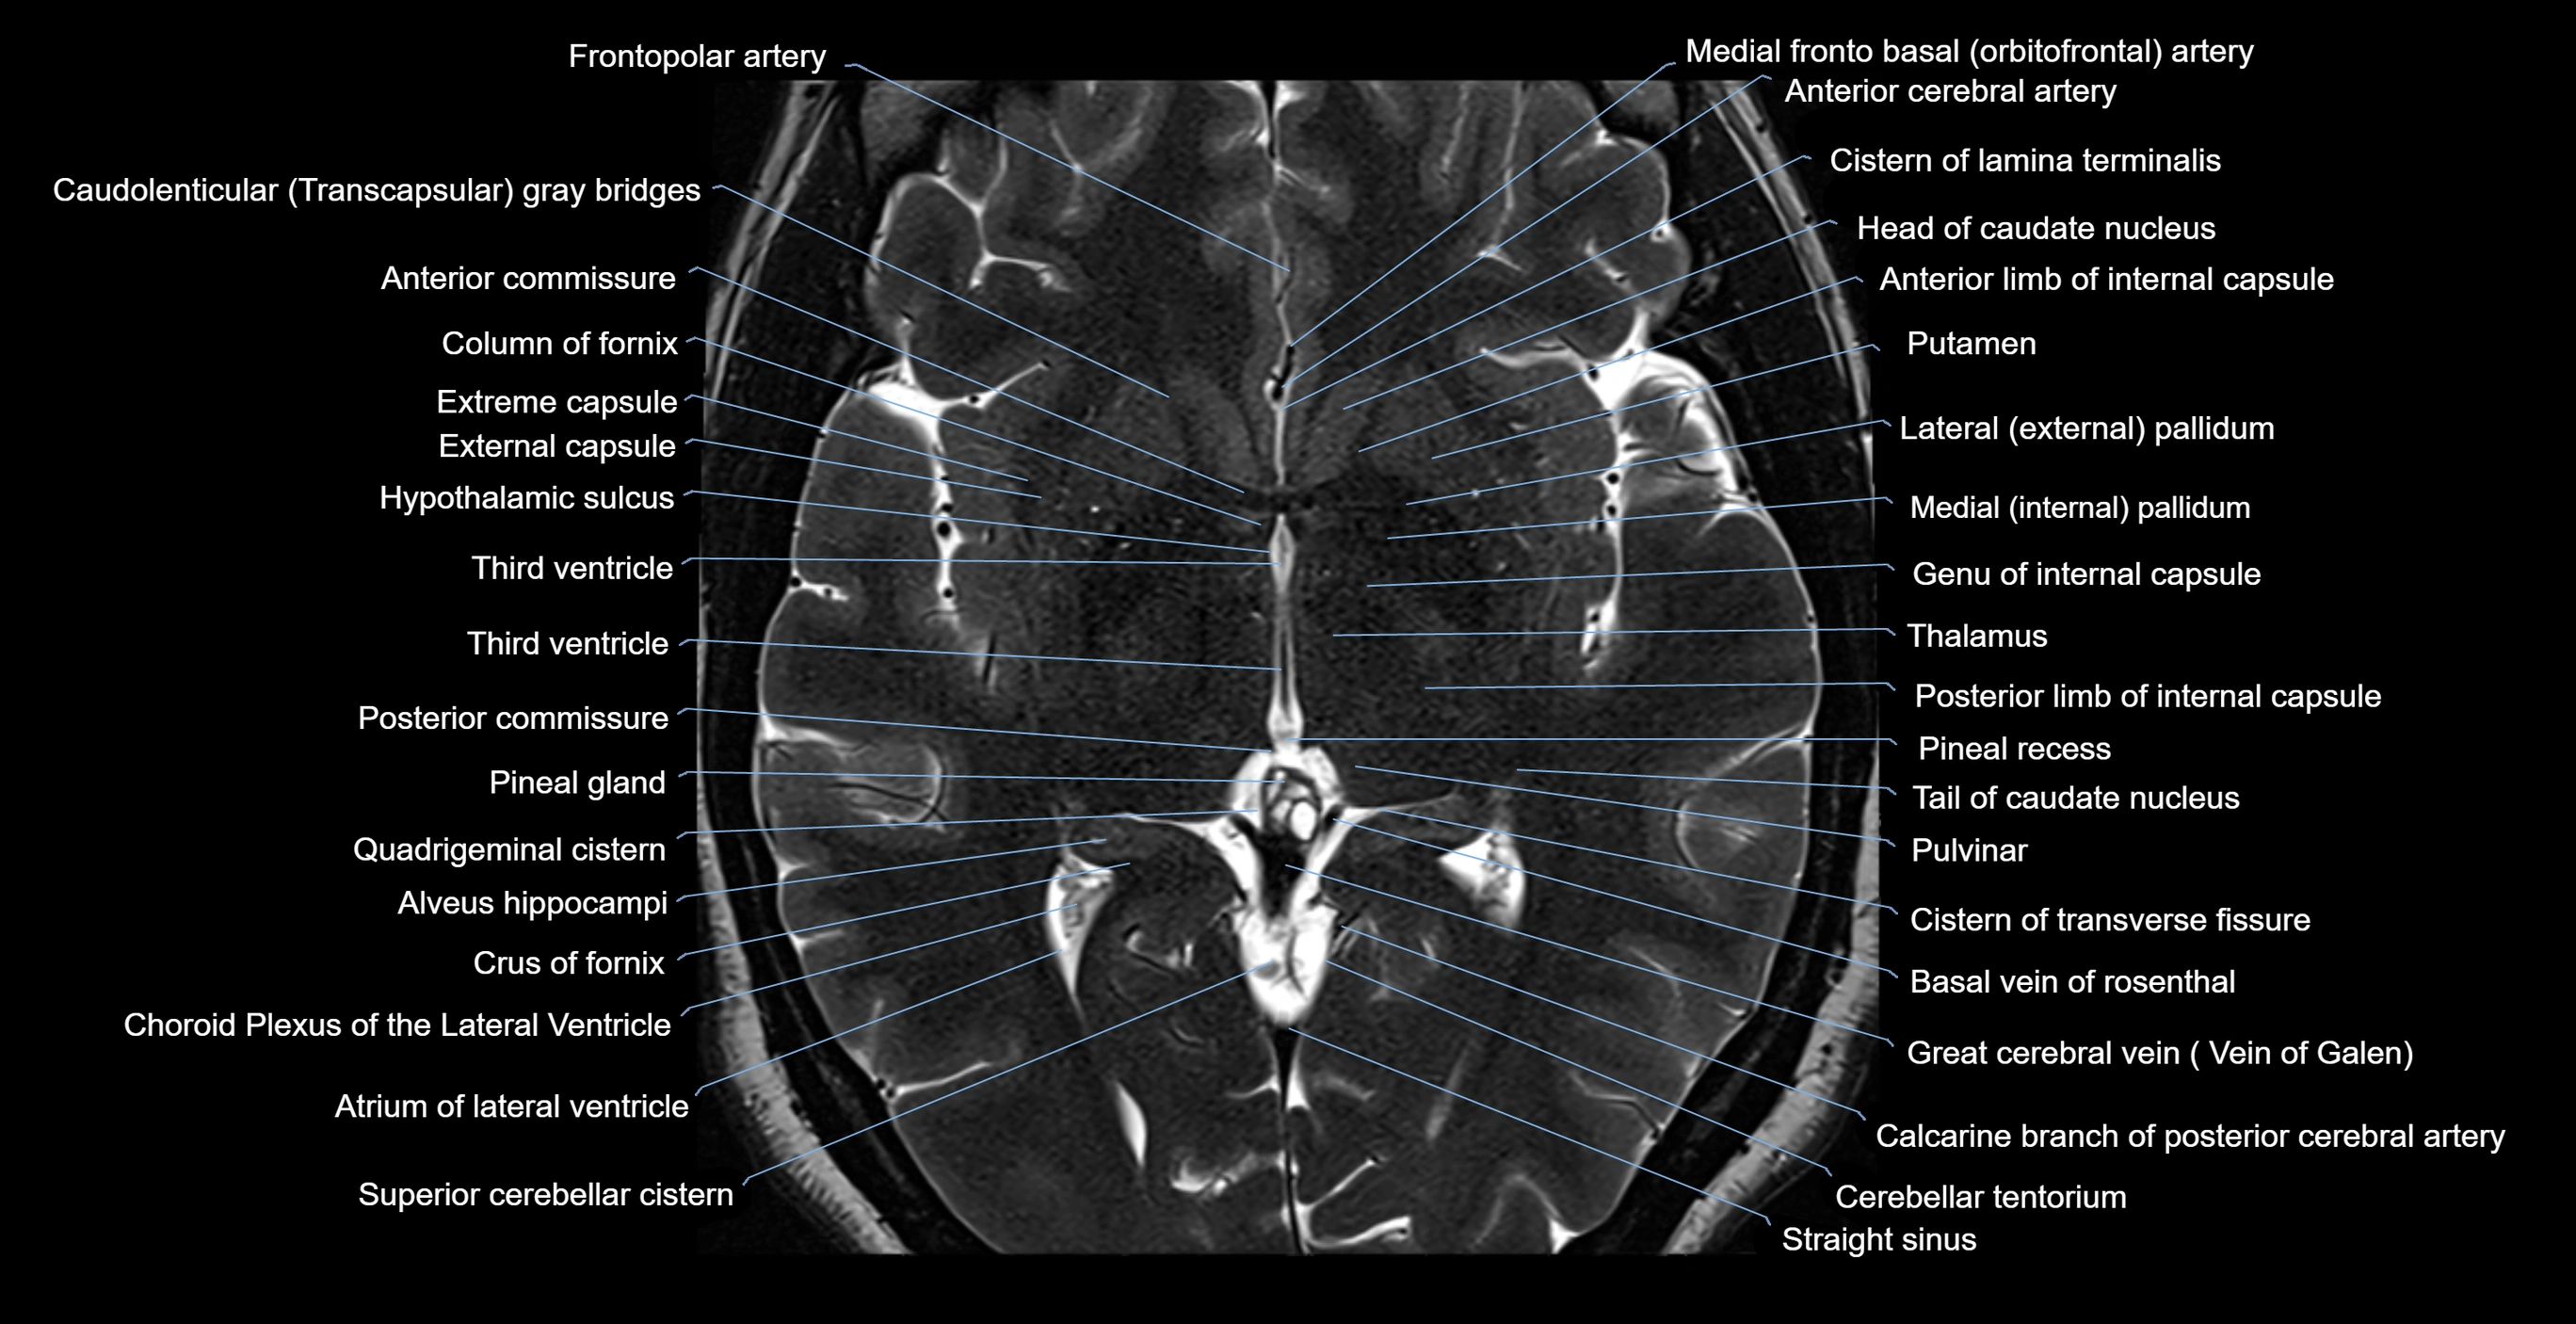

MRI images